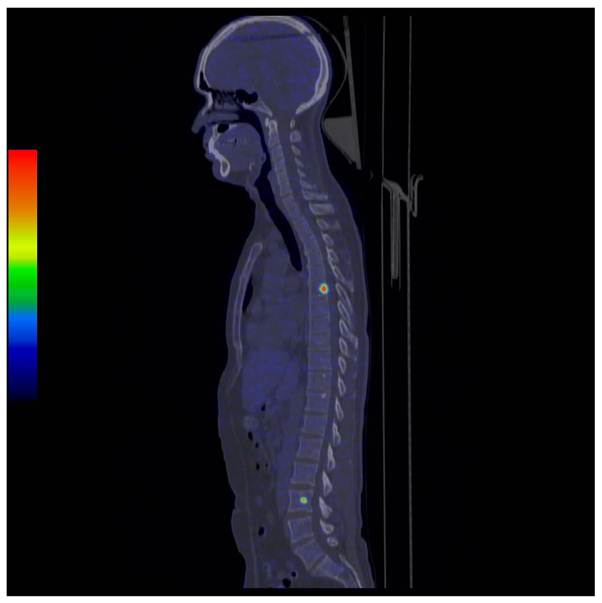

The clinical impact of FDG-PET/CT is perhaps most obvious in the evaluation of non-small cell lung cancer (NSCLC) and is currently regarded as a first-line requirement for optimal patient care.[4] There are several reasons for using FDG-PET/CT in the evaluation of cancer, as can be seen in Figure 1. The finding of a suspicious lung nodule in CT combined with an elevated FDG uptake has a high sensitivity detecting a cancerous growth in the lesion (Figure 1, A). Such a patient needs urgent treatment. On the other hand, a similar lesion in CT associated with an absence of FDG uptake has a very high negative predictive value (Figure 1, B) and this patient could be subjected to watchful waiting.

Figure 1

Lung cancer. Transaxial images of CT (left) and FDG-PET/CT (right) in three different patients. A: A male smoker with 2 cm lump in left lung (red cross hair). With CT alone the risk of this lump being cancer is 50%. The lump has a very high FDG uptake, which is typical for fast growing cancers and the combined image indicates an 80% risk of cancer. B: A non-smoking female with a 1.5 cm lesion that has no FDG uptake (the large yellow area is the heart muscle). The negative predictive value of the combined image is 99%. C: CT with a bone window setting is negative for bone metastases. PET shows two small metastases with very intense uptake. This pattern indicates infiltrative growth in the bone marrow with minimal destruction of bone structure and might precede positive findings on CT alone by several months.

In case the lung lesion is confined, the patient is potentially curable by surgery. However, lung cancer often metastasizes early. For this reason, modern FDG-PET/CT imaging evaluates larger parts of the body, typically from the base of the skull to the mid-thighs, and has a very high sensitivity for detecting spread disease. The PET images show more metastatic lesions than any other imaging modality (Figure 1,C).